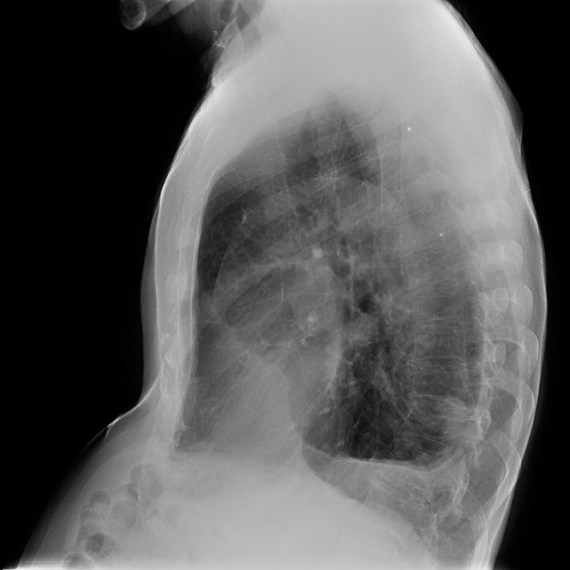

CASO: Febrícula y tos de 4 días de evolución.

Hallazgos:

- En la placa PA se observa una asimetría en los hilios pulmonares, el hilio izquierdo tiene una densidad aumentada.

- Tras examinar la placa lateral se observa un aumento de densidad en la columna que puede ser compatible con una condensación, es el signo de la desnificación vertebral.

SIGNO DE LA DENSIFICACIÓN VERTEBRAL: En la radiografía lateral normal, la densidad de la columna torácica tiende a disminuir desde la parte superior hasta el diafragma; la alteración de ese patrón por la presencia de una densidad superpuesta a la columna, indica la existencia de una consolidación pulmonar. Este signo adquiere especial valor cuando en la proyección posteroanterior la consolidación está oculta en el espacio retrocardíaco o en la base pulmonar.